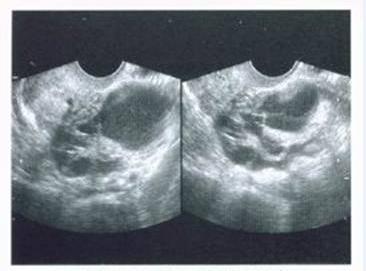

超声下盆腔显影术是近年来开展的一项新技术,能较直观地显示子宫腔、输卵管及输卵管伞端的形态与通透性。方法是用专用显影管置入宫腔,固定,注入无菌混合液在道格拉斯窝形成液区暗区,在超声引导下穿刺并注入适量无菌液体后,经阴道超声可以动态地观察宫腔,输卵管,输卵管伞端的形态与功能是否正常,此项技术用于显示输卵管通畅性及伞端形态,也可用于判断宫腔、内膜的异常,检查结果能帮助医生给患者制定出下一步的治疗方案。

习惯性流产可能由于宫腔内纤维隔或宫腔形态异常所致。这些做普通超声难以发现,但是在超声显影术中就变得清楚了。